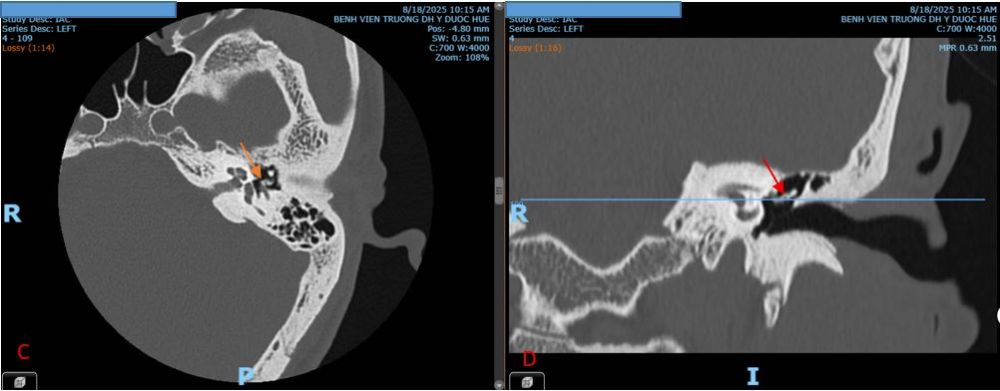

Hình 2. Hình ảnh dị dạng chuỗi xương con tai trái trên CTscan.

Trên mặt phẳng Axial,tai trái cho thấy hình ảnh biến dạng xương bàn đạp, mất khoáng cửa sổ bầu dục (mũi tên màu cam). Trên mặt phẳng Coronal tai trái thấy hình ảnh dị dạng cành xuống xương đe (mũi tên màu đỏ).A,B. Tai phải; C,D. Tai trái